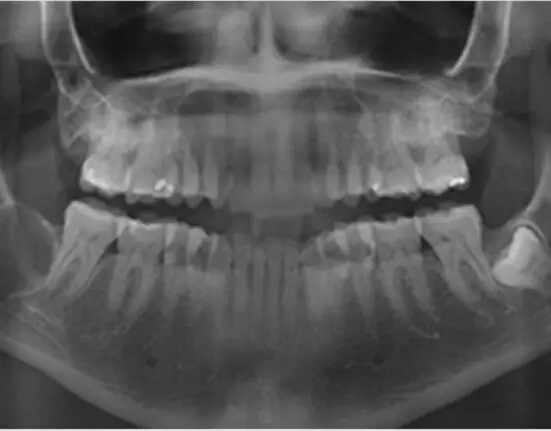

The calcification of the carotid artery is a sign of advanced arteriosclerosis, which may be associated with chronic coronary artery disease (CAD) and can lead to death. Such calcification can be seen in regular oral panoramic radiography, according to a multi-institute team of researchers from Finland and Sweden.

The researchers found carotid artery calcification in 102 patients (20.7%), with 81 moderate cases (16.4%) and 21 severe cases (4.3%). Calcification was considered severe when the deposit was more than 10 mm in diameter. In statistical analyses, the patients’ age, gender, smoking habits, diabetes, disturbances of lipid metabolism (or dyslipidemia), and blood pressure were considered.

“Oral infections are fairly common, but they are often latent and found only through radiography. Radiographs of the whole jaw conducted in conjunction with dental care can reveal a cardiovascular disease risk as an incidental finding. If carotid artery calcification is seen in the radiograph, the patient must be referred to further examinations and an assessment of the need for treatment,” Pussinen said.